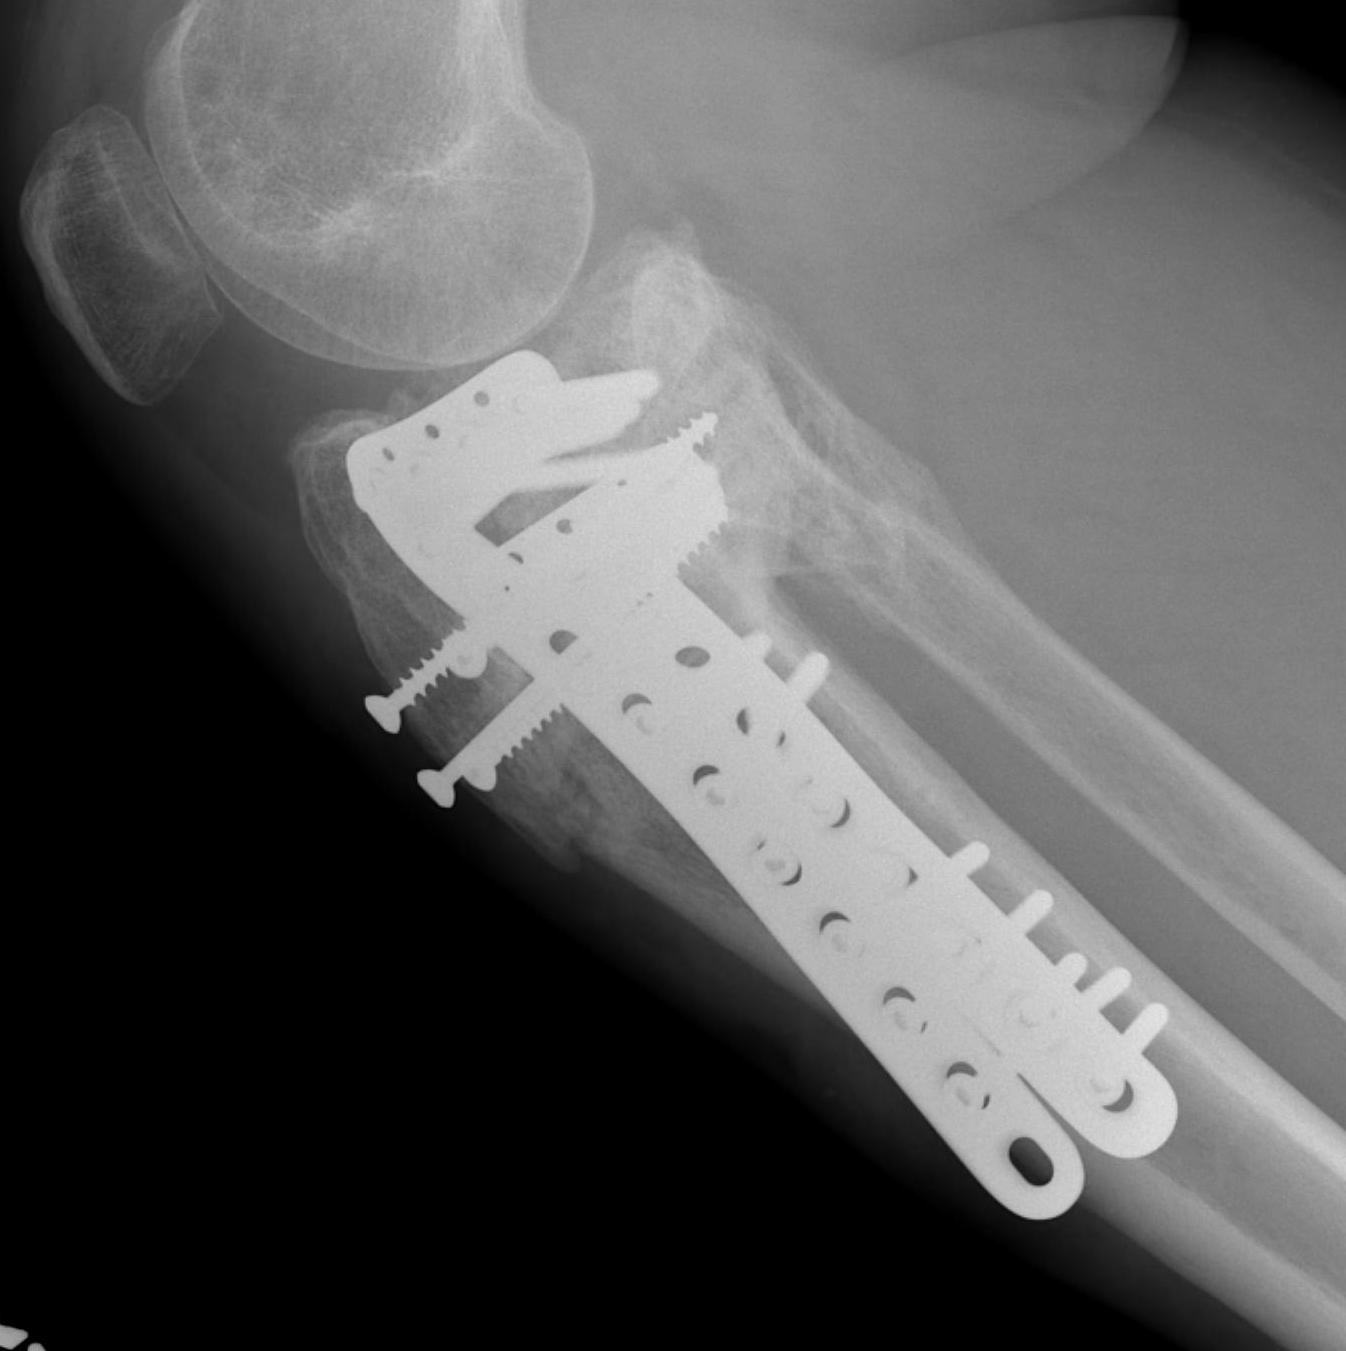

Type VI Bicondylar with Metaphyseal Fracture

Technique

- long locking plate minimally invasive with locking jig / MIPO

- proximal lag screws

- ensure correct alignment

- often use small medial buttress plate